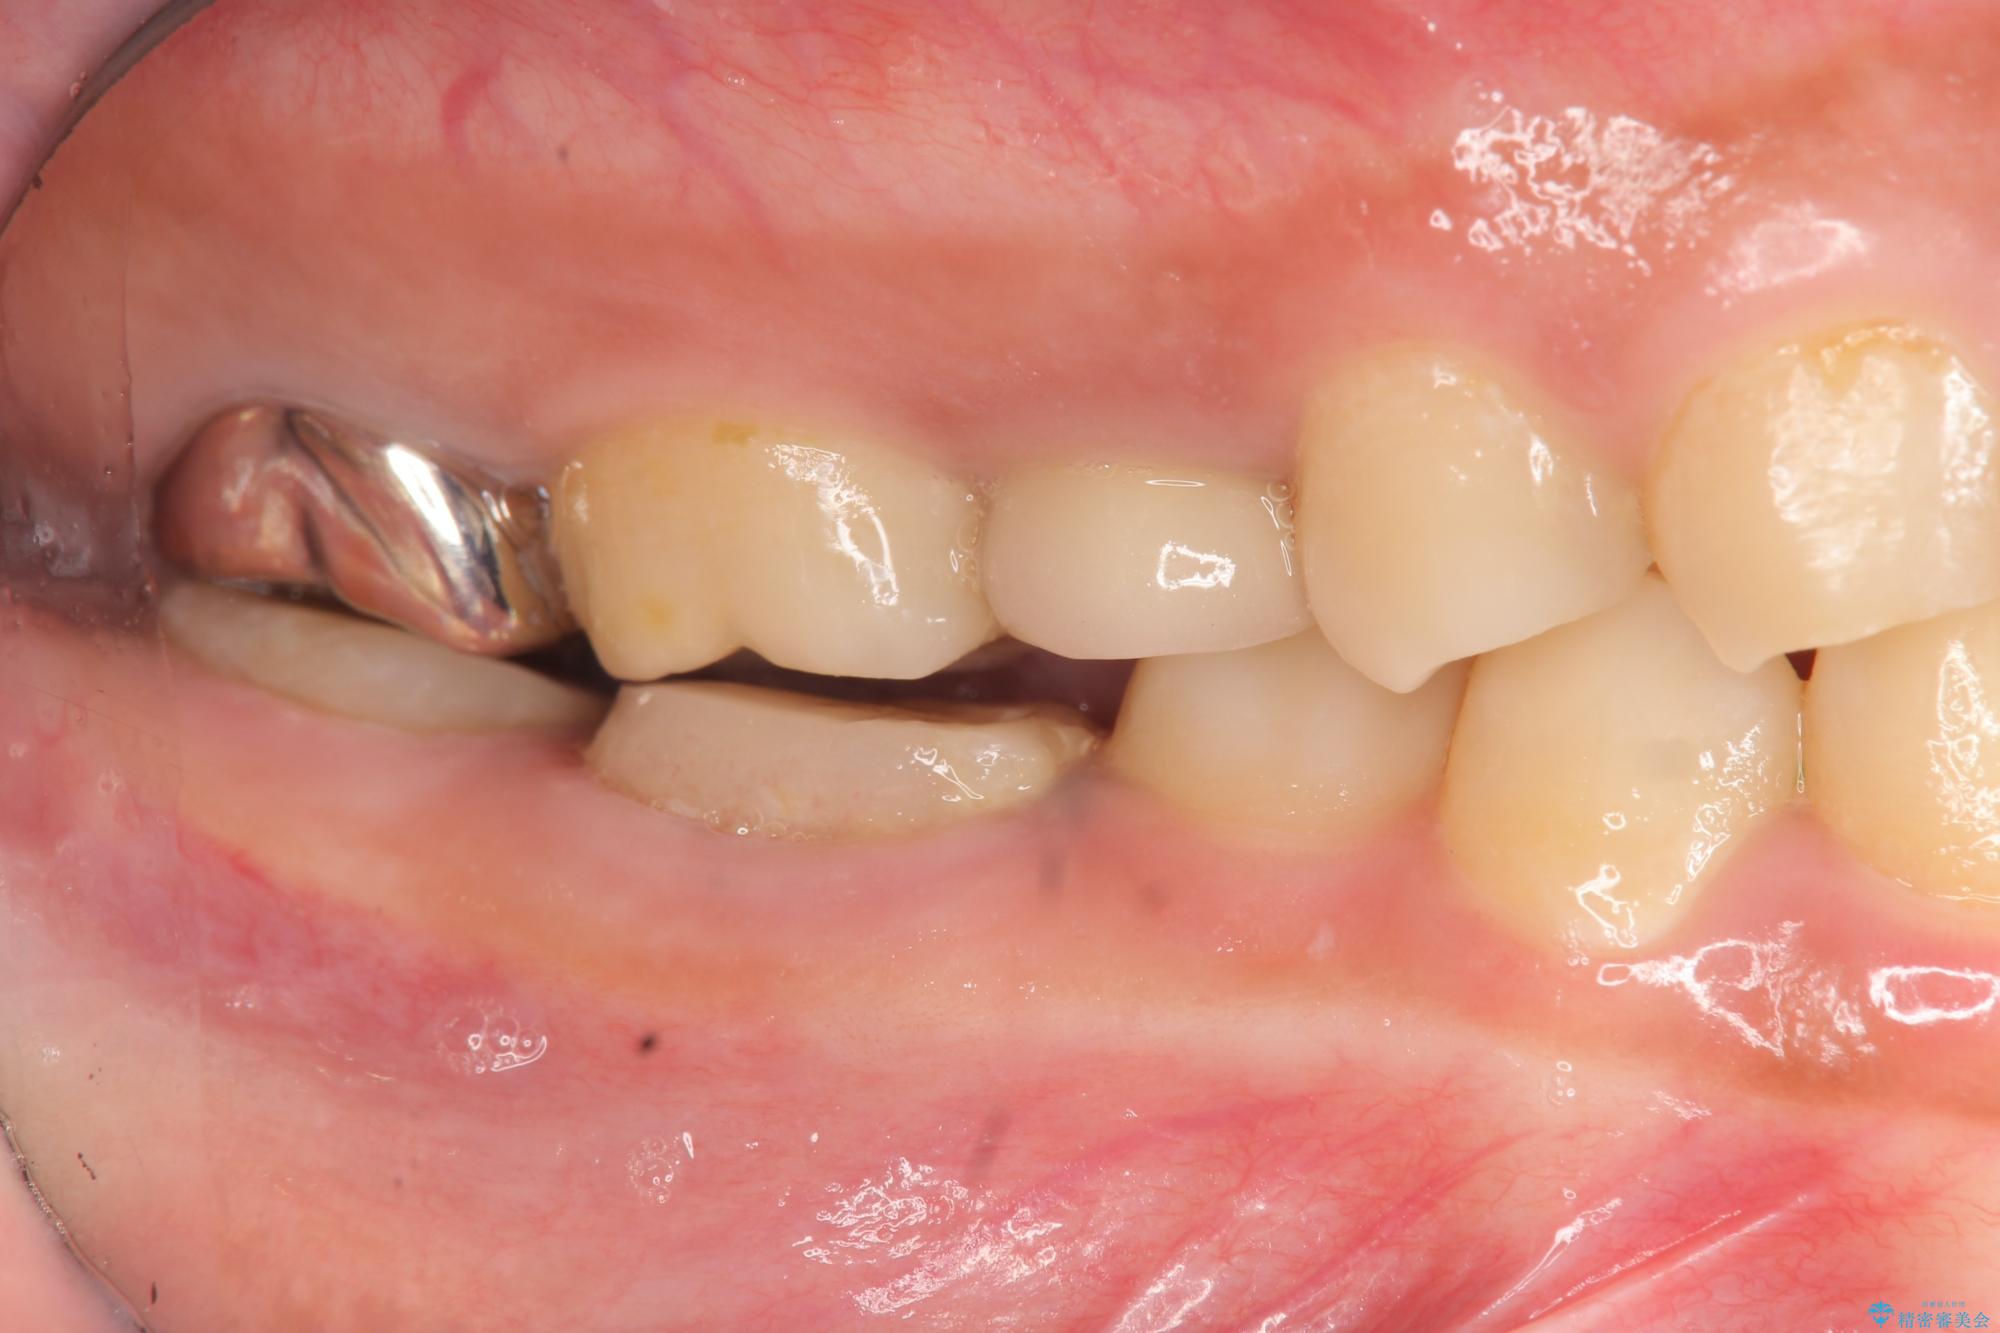

奥歯は既に根管治療が為されクラウンを装着する必要性がある状態ですが、歯の高さが低くクラウンの安定性・強度を担保するために歯周外科を行う治療計画としました。

歯周外科を行うことで、歯ぐきの位置を下げ歯の高さを作り出し安定したクラウンの装着が可能となります。また同時に舌の邪魔となっていた骨隆起の除去を行うこととしました。

- 37.4万円(ジルコニアクラウン×2・仮歯×2・歯周外科手術)費用は治療当時の料金となります